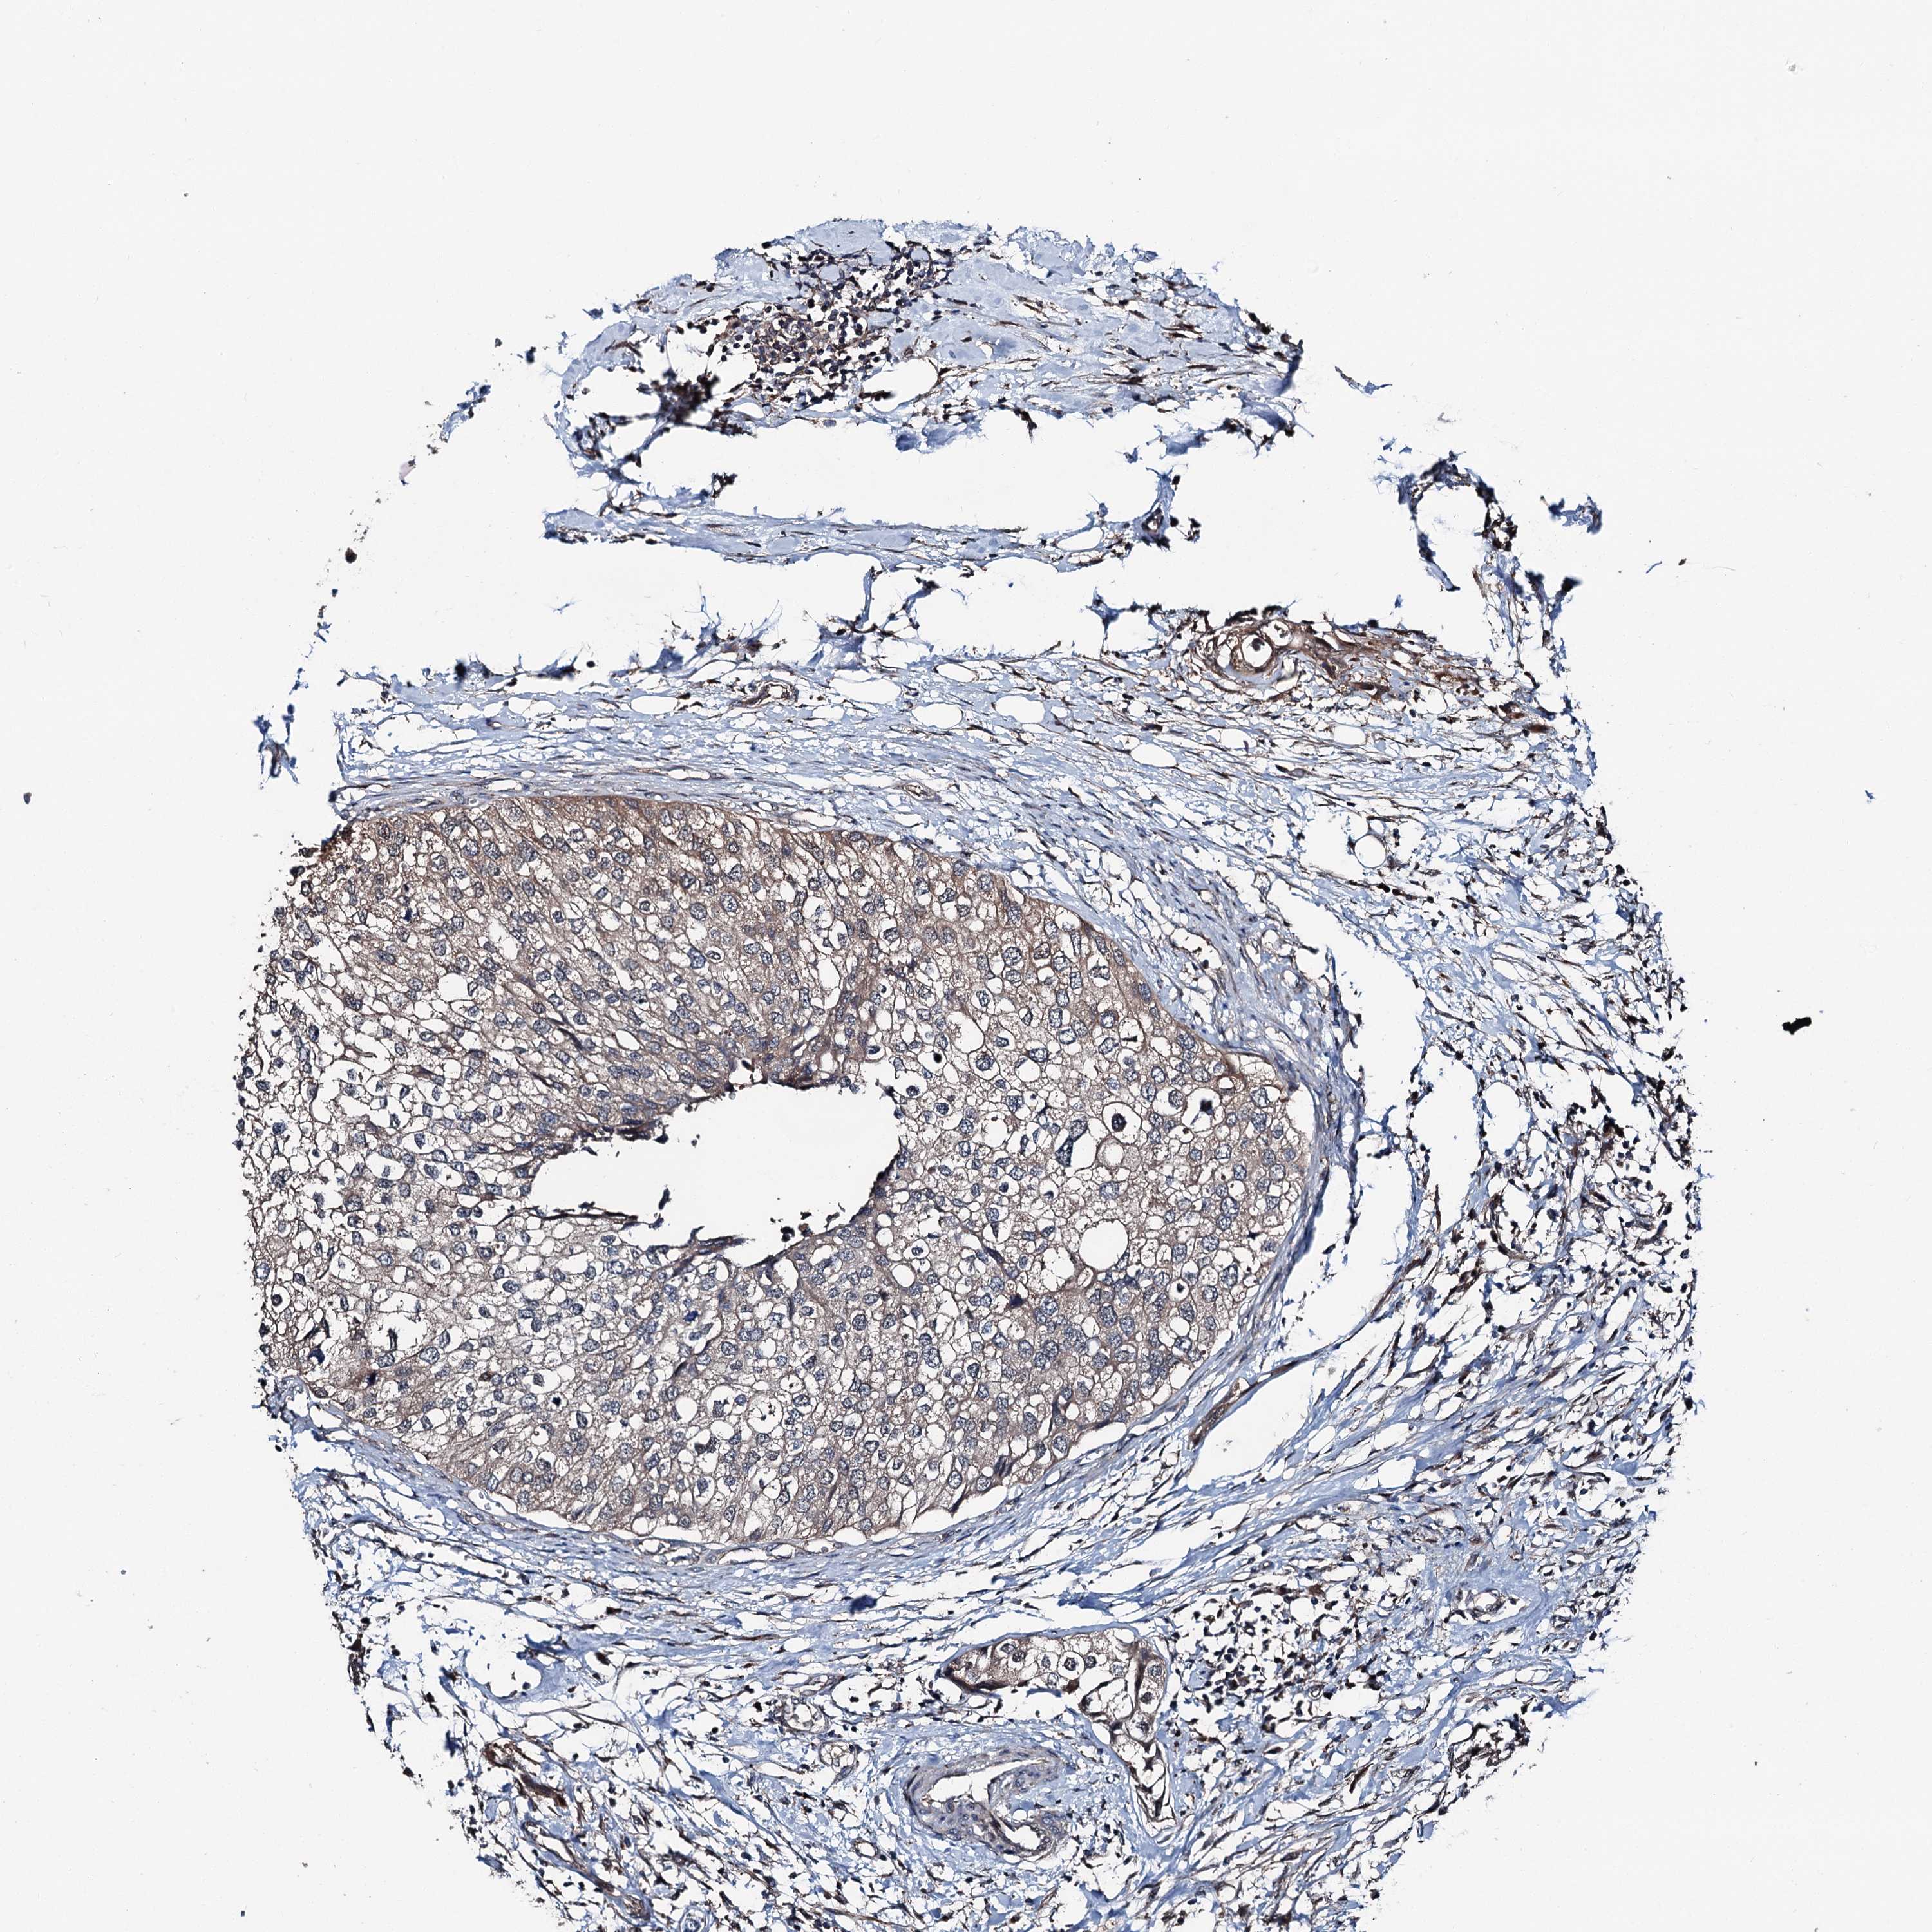

UROTHELIAL CANCER - Protein expressioni

A mouse-over function shows sample information and annotation data. Click on an image to view it in a full screen mode. Samples can be filtered based on level of antibody staining by selecting one or several of the following categories: high, medium, low and not detected. The assay and annotation is described here.

Note that samples used for immunohistochemistry by the Human Protein Atlas do not correspond to samples in the TCGA dataset.

Antibody stainingi

Antibody staining in the annotated cell types in the current human tissue is reported as not detected, low, medium, or high, based on conventional immunohistochemistry profiling in selected tissues. This score is based on the combination of the staining intensity and fraction of stained cells.

Each image is clickable and will lead to virtual microscopy that enables deeper exploration of all samples and also displays staining intensity scores, fraction scores and subcellular localization as well as patient and tissue information for each sample.

Antibody HPA038691

Antibody HPA038692

Urothelial carcinoma, High grade

Urothelial carcinoma, Low grade